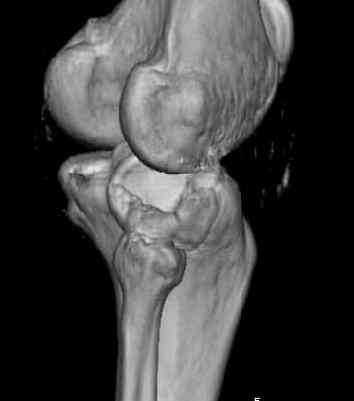

Здравствуйте, уважаемые коллеги!Подскажите, пожалуйста, какой выбрать доступ и способ фиксации при импрессионном переломе заднего отдела наружного мыщелка большеберцовой кости. Женщина 40 лет, травму получила 02.01.2008, катаясь на горных лыжах.Есть ли здесь необходимость использовать задний доступ, или можно справиться через наружный? Есть ли шансы сделать закрыто - под ЭОП через медиальное "окошко" поднять забойником суставную поврехность? Какой лучше использовать фиксатор?Спасибо.

центральная импрессия, а при ипрессии с краевым переломом - после приподнимания импрессии опорная (Butress) пластина, как на снимке.

In this situation, where the fragment is posterolateral, one needs a posterior approach, either as described by Timothy Bhatacharya et al in 2005 in JOT, which involves taking down the medial head of the gastrocnemius, or the Lobenhoffer paper which involves a transfibular approach.